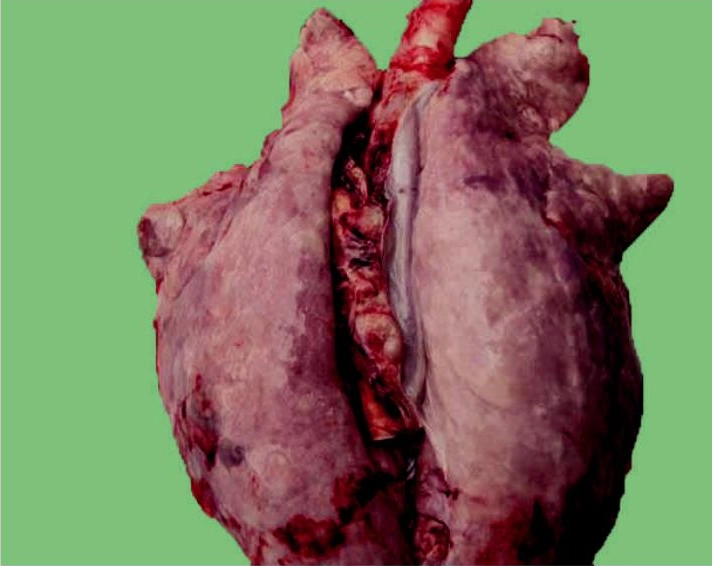

Hình ảnh bệnh tụ huyết trùng ở lợn

- Viêm màng phổi, phổi xuất huyết